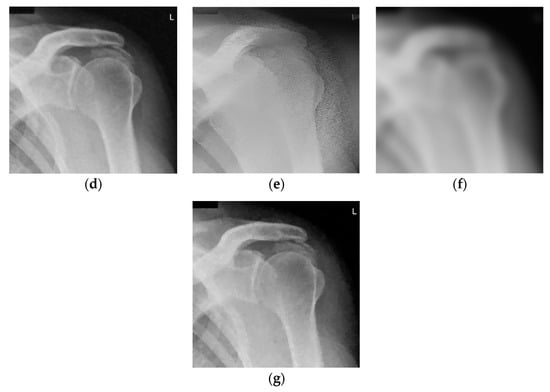

Denoised ankle X-ray images (with resolution 600 × 682) are given in Figure 5. Figure 5a,b show noise-free and noisy images, respectively. Figure 5c–e shows the denoised images obtained using the 2D LPA-RICI method with quadrilateral, octagonal and hexadecagonal regions, respectively.

Figure 5.

Ankle X-ray scan. (a) Original noise-free image; (b) Noisy image (AWGN with σ = 25); (c) Image denoised using the 2D LPA-RICI method (quadrilateral region, Г = 1.8, Rc = 0.8); (d) Image denoised using the 2D LPA-RICI method (octagonal region, Г = 1.8, Rc = 0.8); (e) Image denoised using the 2D LPA-RICI method (hexadecagonal region, Г = 1.8, Rc = 0.8); (f) Image denoised using Gaussian smoothing filters; (g) Image denoised using total variation denoising.

Table 5 gives the PSNRs of the denoised ankle X-ray images. The proposed 2D LPA-RICI method, as it was the case for other two test images, outperformed fixed size 2D filtering in all cases. Furthermore, it also increased the denoised image PSNR when compared to the Gaussian smoothing filters and the total variation denoising (when quadrilateral or octagonal regions were used).

As it can be seen from Table 6, ankle X-ray scan denoised by the 2D LPA-RICI method with quadrilateral regions resulted in an increased PSNR (compared to the noisy image) by up to 8.09 dB, by up to 7.46 dB with octagonal regions and by up to 3.93 dB with hexadecagonal regions. Once again, the proposed 2D LPA-RICI method was shown to significantly outperform the fixed size 2D median filtering. In addition, it also outperformed Gaussian smoothing filter method for all tested regions (including hexadecagonal regions, which was not the case in the previous examples) by up to 5.46 dB. Furthermore, it increased the denoised PSNR when compared to the total variation denoising method by up to 2.80 dB (when quadrilateral and octagonal regions were used).